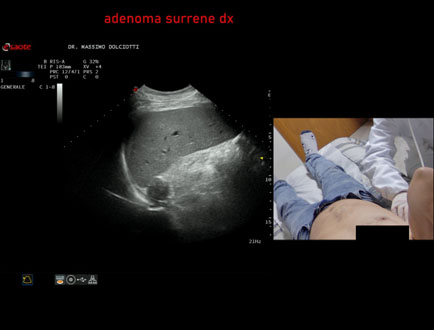

Data inserimento: 06/11/2025

Ecografia del: 31/10/2025

Strumento: Esaote MyLab Eight

Sonda: Convex Multifrequenza 1-8 MHz

Età Paziente: F 69 anni

Motivazione dell'esame: follow up per piccolo adenoma surrenalico.

Commento all'esame: le immagini ed il video documentano in sede surrenalica destra, formazione ipoecogena, a margini definiti, rotondeggiante, delle dimensioni di 15,8 x 14,8 mm, da ricondurre ad adenoma surrenalico.

Conclusioni: piccolo adenoma surrenalico destro (small right adrenal adenoma).

Presentazione: Dr. Massimo Dolciotti - Ancona

Elaborazione digitale: Andrea Dini - Ancona